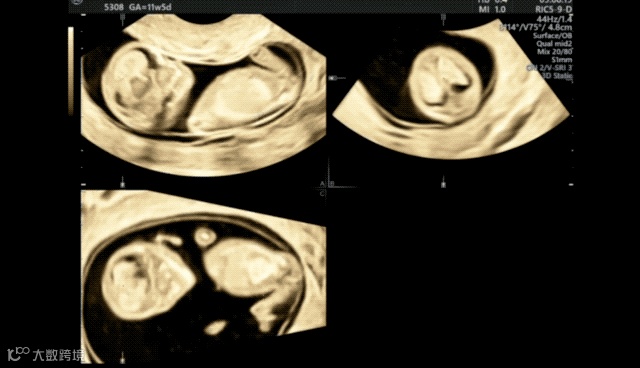

在超声机菜单上选取muti-plane、四幅画面,获得这张图。muti-plane多平面模式不同于render渲染模式,渲染模式下选择单幅画面只会显示3维图像,多平面模式就可以单独放大abc平面。

A平面是胎儿矢状切面,B平面是胎儿横切面,c平面是胎儿冠状切面。单纯旋转a切面很难获取标准正中矢状切面的,我们需要借助bc平面,只要bc平面标准了,a平面也自然是标准了。所以bc平面要选择能够快速识别是否标准的标志物,这里我选择了大脑镰,目标是b平面上大脑镰绝对垂直、c平面上大脑镰绝对平行,这样我们的a平面就是胎儿正中矢状切面了

适当放大图像,在a 平面移动观察点,让b平面容易辨认

在b平面移动观察点,让c平面容易辨认,注意b平面的观察点要放在大脑镰上,这样当b平面垂直后,才能在a平面上显示的是正中矢状切面。

在点选a平面情况下,旋转xy轴,让bc平面达到我们预期的位置,就可以看到a平面已经基本显示出正中矢状切面了。

微调后,我们在菜单内选择a平面-单幅图像,放大,就可以测量头臀长。